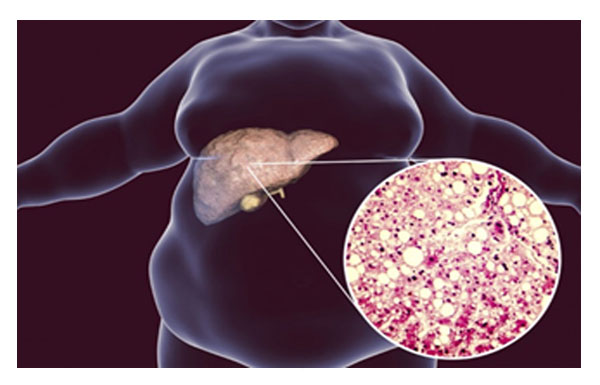

Non-Alcoholic Fatty Liver Disease is increasingly common worldwide and linked to obesity, diabetes, and metabolic syndrome. Recent research underscores that MASLD treatment centers on lifestyle modification and drug therapies targeted at metabolic risk factors.